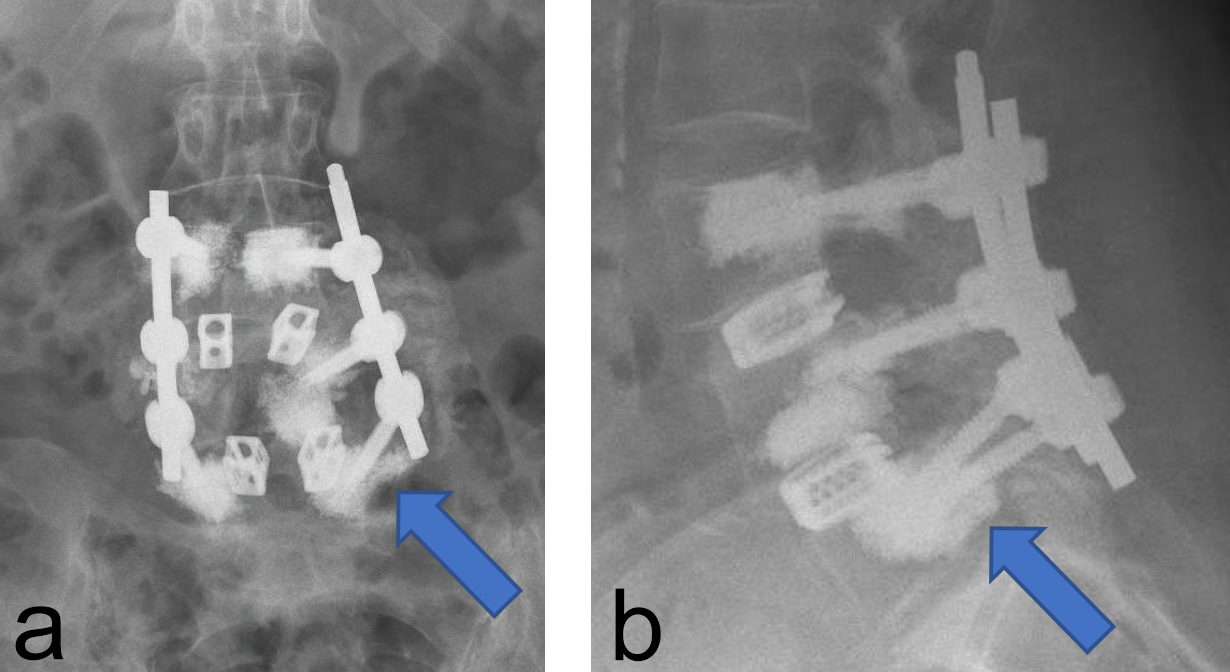

Two other patients had cement leakage into the neuroforamen which caused motor and sensory dysfunction of the affected nerve root. In retrospect the chosen screw length was too short for the vertebra; therefore, the most posterior located perforation in the screw was located within the pedicle (Fig 2).

Instrumentation failure occurred in 7 (11.5%) of 61 patients. One patient developed loosening of the three most caudal nonaugmented screws in a long fusion construct. Two patients had screw loosening after a proven infection (one of them with augmented screws). One developed screw loosening due to a pedicle fracture. Another had CAPS loosening after traumatic fracture of the L5 vertebral body (Fig 3). Two patients had a screw breakage. In total 3 (0.86%) of 233 cement- augmented pedicle screws in 61 patients failed despite cement augmentation (Table 2).